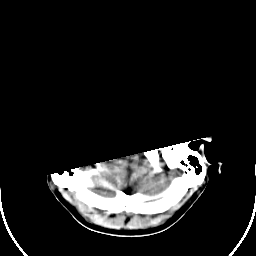

Sarcoma: Roentgen-ray CT -- Slice #3

[Home][Help][Clinical] Slice 3